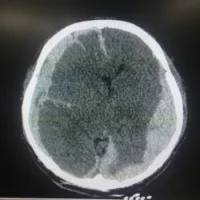

HOW DOES A TRAUMATIC BRAIN INJURY AFFECT A PERSON’S LIFE?

While any type of injury resulting from an accident can be painful and affect day-to-day living, traumatic brain injuries (TBIs) can have lifelong consequences. From affecting thought and mood to the ability to walk, our brains control every aspect of our life. Any form of head injury can have a significant impact on a person’s quality of life.